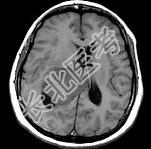

- 单项选择题女,45岁, 右眼视力下降8个月,右颜面麻木半个月, 时有头昏,味觉减退, 请根据所提供图像,选择最可能的诊断是 ( )

A、(右侧脑室)胶质瘤

B、(右侧脑室)脉络膜乳头状瘤

C、(右侧脑室)转移瘤

D、(右侧脑室)室管膜瘤

E、(右侧脑室)脑膜瘤(合体细胞型)